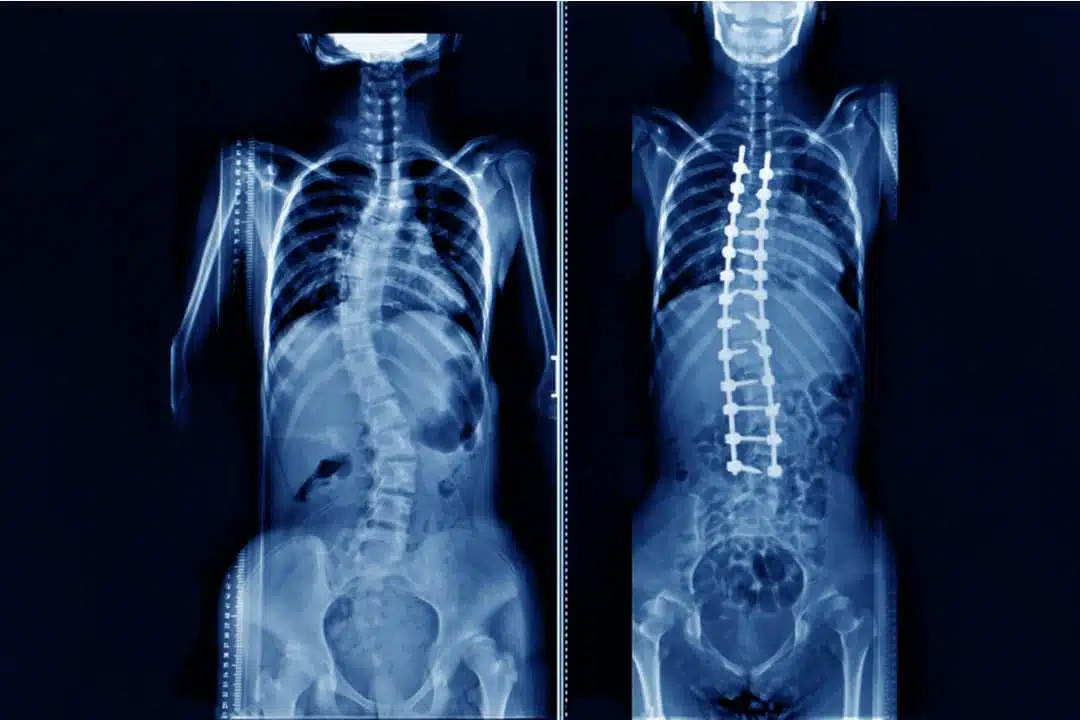

3. علاج الجنف عن طريق الجراحة

عندما تصل درجة الجنف لمراحل متقدمة 40 أو 50 درجة ، ينصح الأطباء المريض بإجراء الجراحة، سواء كان المريض مراهقاً أم بالغاً. يوصى بالإجراء الجراحي عندما تكون درجة المنحنى 50 وعندما يعاني المريض من تلف الأعصاب في الساقين أو الوعاء أو يسبب مشاكل في المثانة. عادة ما تتطور حالات الجنَف الحادة بمرور الوقت، لذا فإن طبيبك قد يقترح إجراء جراحة الجنَف لخفض حدة انحناء العمود الفقري ولمنع تفاقم الحالة. إن أحد أكثر أنواع جراحة الجنف شيوعاً تسمى دَمْج الفقرات.